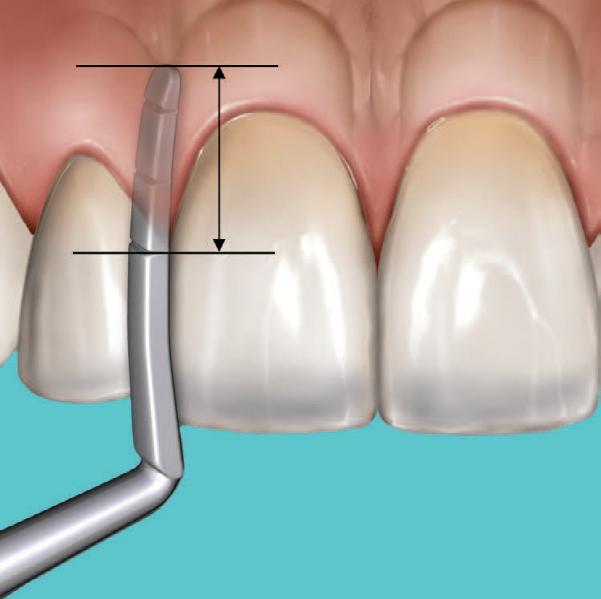

A significant number of people are unhappy with their smile, which has a considerable psychosocial impact. Although many seek cosmetic dental treatment, costs, fear and duration of total treatment are often barriers to the patients. Nevertheless, many could benefit from small and subtle changes to their teeth. With simple direct and freehand techniques, quick but significant results can be obtained that ultimately greatly improve the overall smile aesthetics.

The restoration of abfractions in the anterior area is important for aesthetic appearance especially in patients with high smile lines. Moreover, restoring abfractions strengthens the cervical area of the tooth, prevents further loss of enamel and ameliorates unpleasant sensitivity.

Black triangles and diastemas can cause entrapment of the food and accumulation of bacteria, which leads to gingivitis and ultimately periodontitis. By eliminating the black triangles and diastemas with composite bonding, the dentist not only improves the aesthetics, but also protects the long-term health of the periodontal tissues.

Worn canine cusp restoration is of special functional importance. Creating functional canine guidance with a minimally invasive composite addition to the canine cusp will protect the posterior teeth during lateral movements of the jaw. Incisal wear restorations return the youthful appearance to the smile and prevent further loss of enamel and exposure of the dentinee.